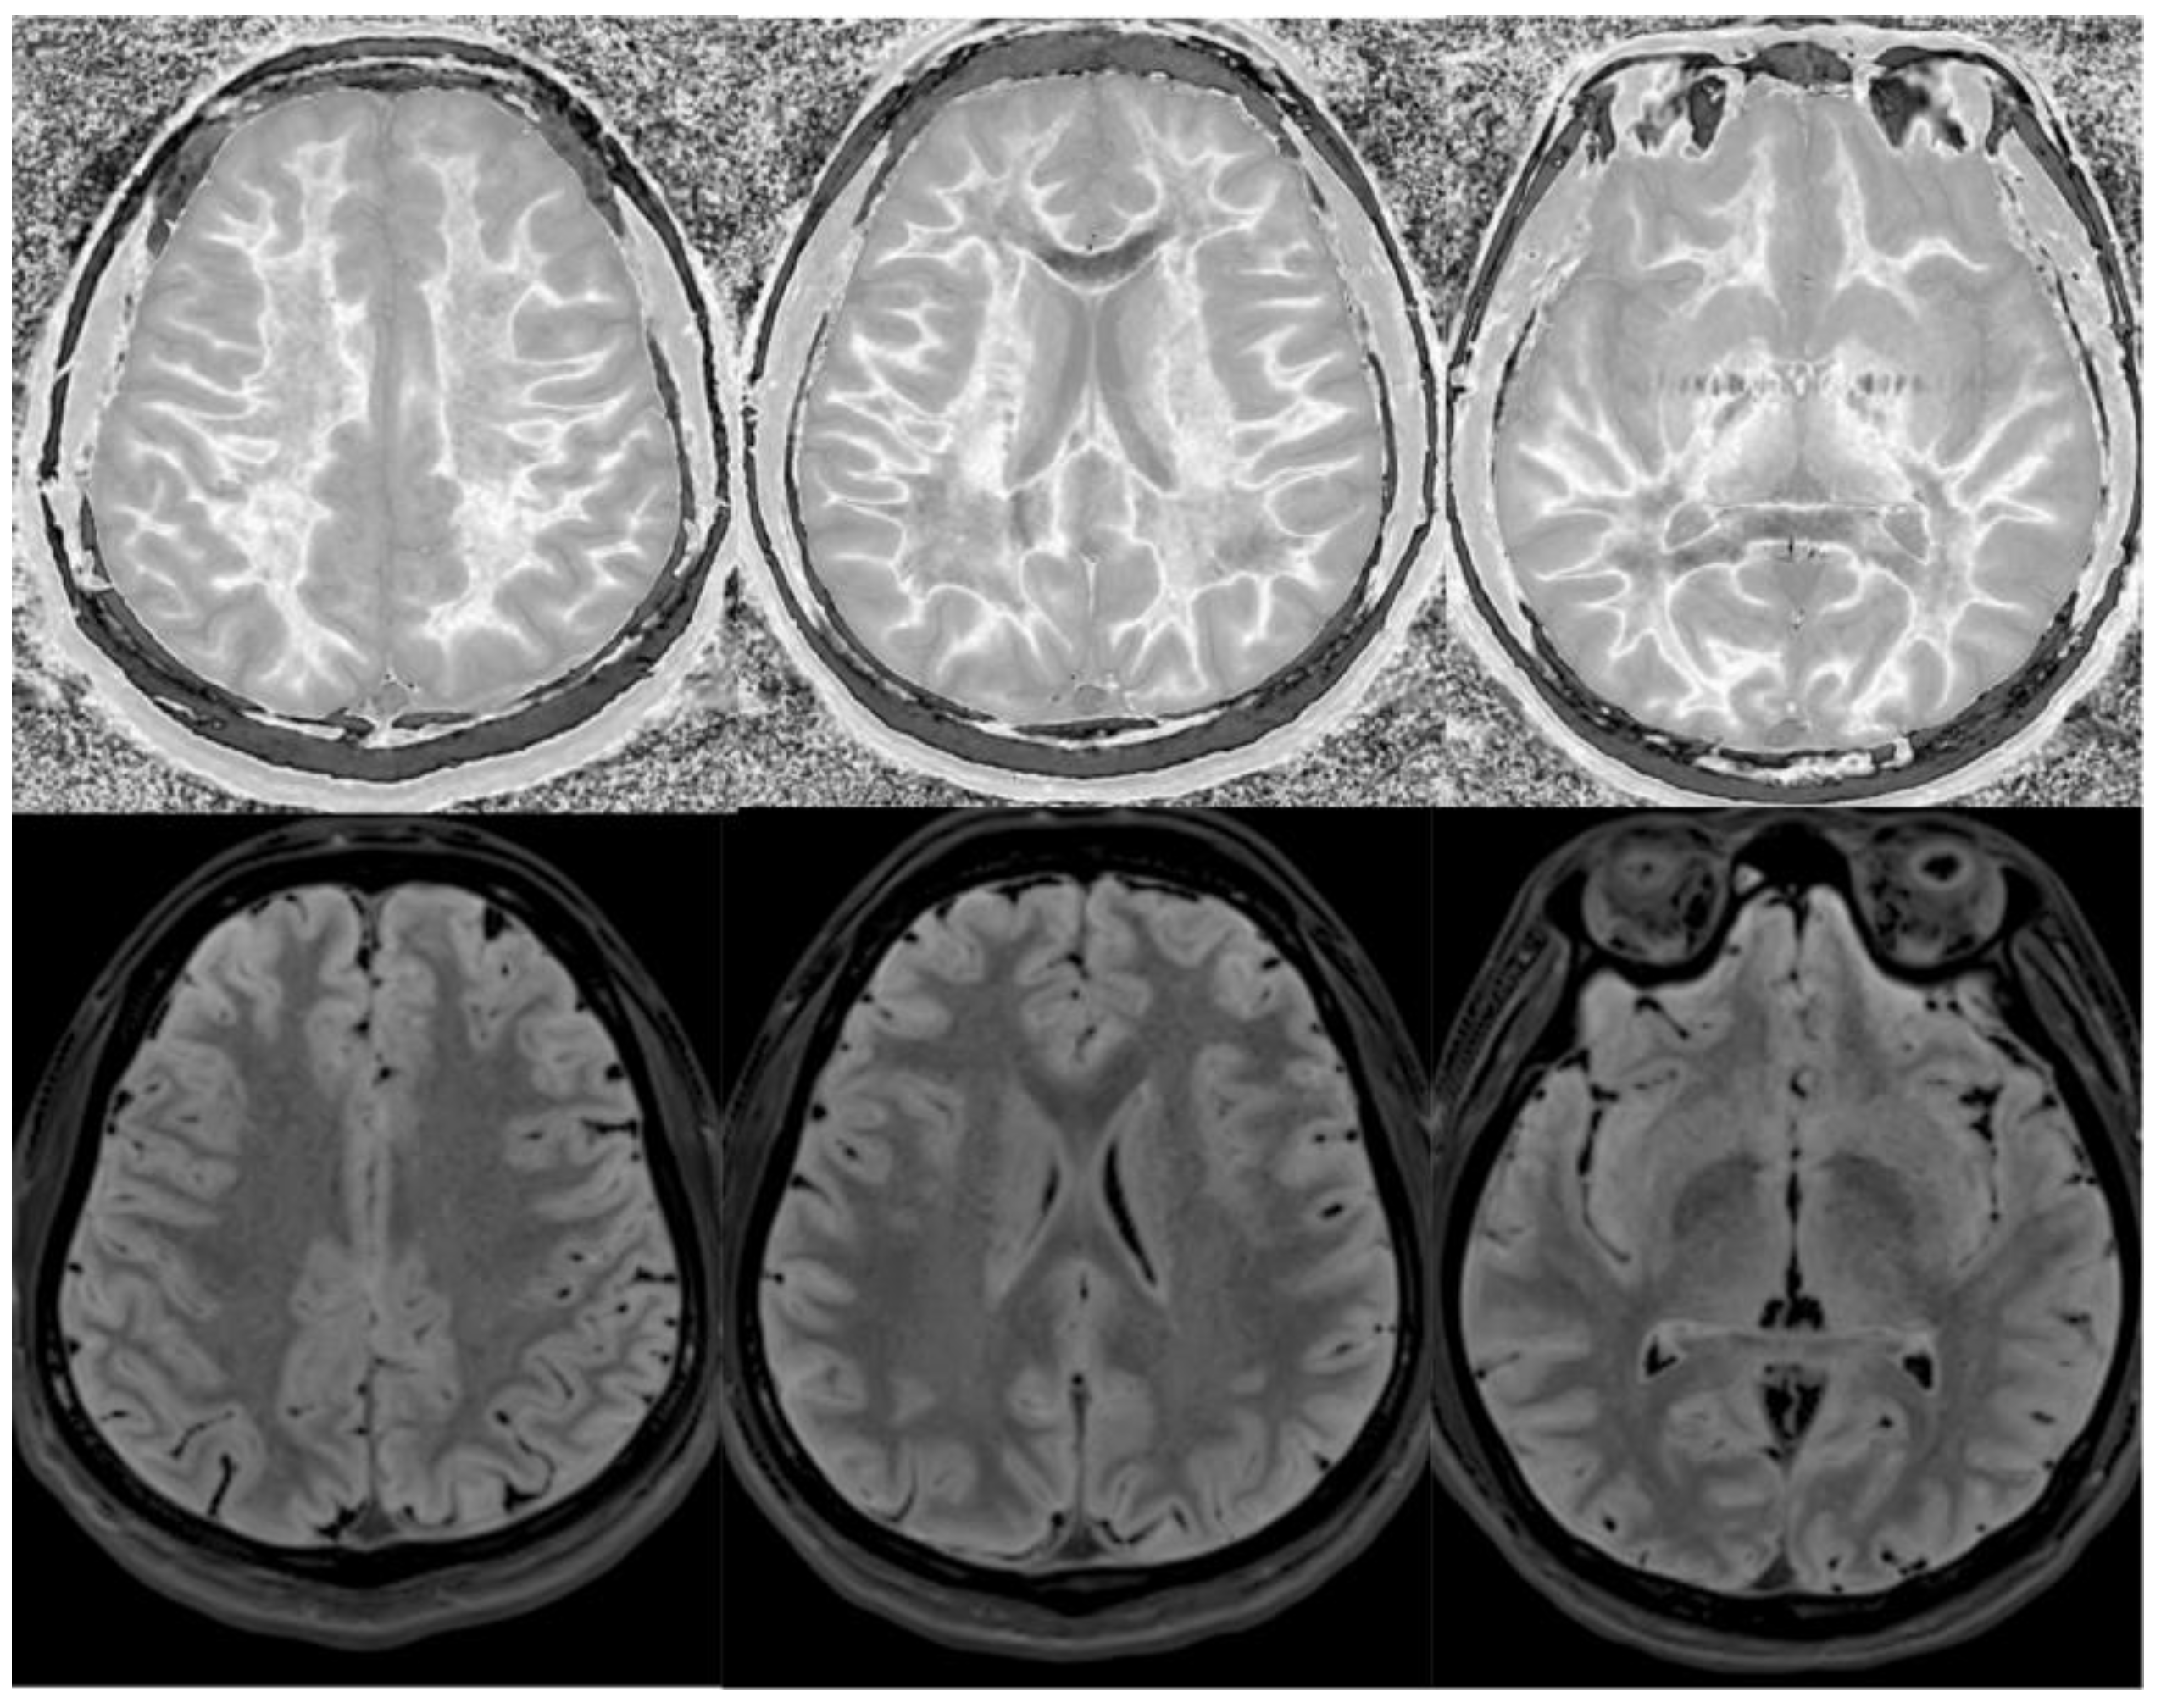

Figure 13.

Divided Subtracted Inversion Recovery (dSIR) in a patient with multiple sclerosis (MS). Three axial narrow middle domain images in a patient with an acute MS flare at the level of the centrum semiovale (left), corona radiata (middle), and basal ganglia (right). TIshort = 350 ms. TIlong = 500 ms. TE = 7 ms, TR = 5000 ms. The white matter is not black as in Figure 9b. There is a widespread increased signal, though not a “white out” sign as described in Figure 14. This is an “intermediate” appearance but not considered normal.